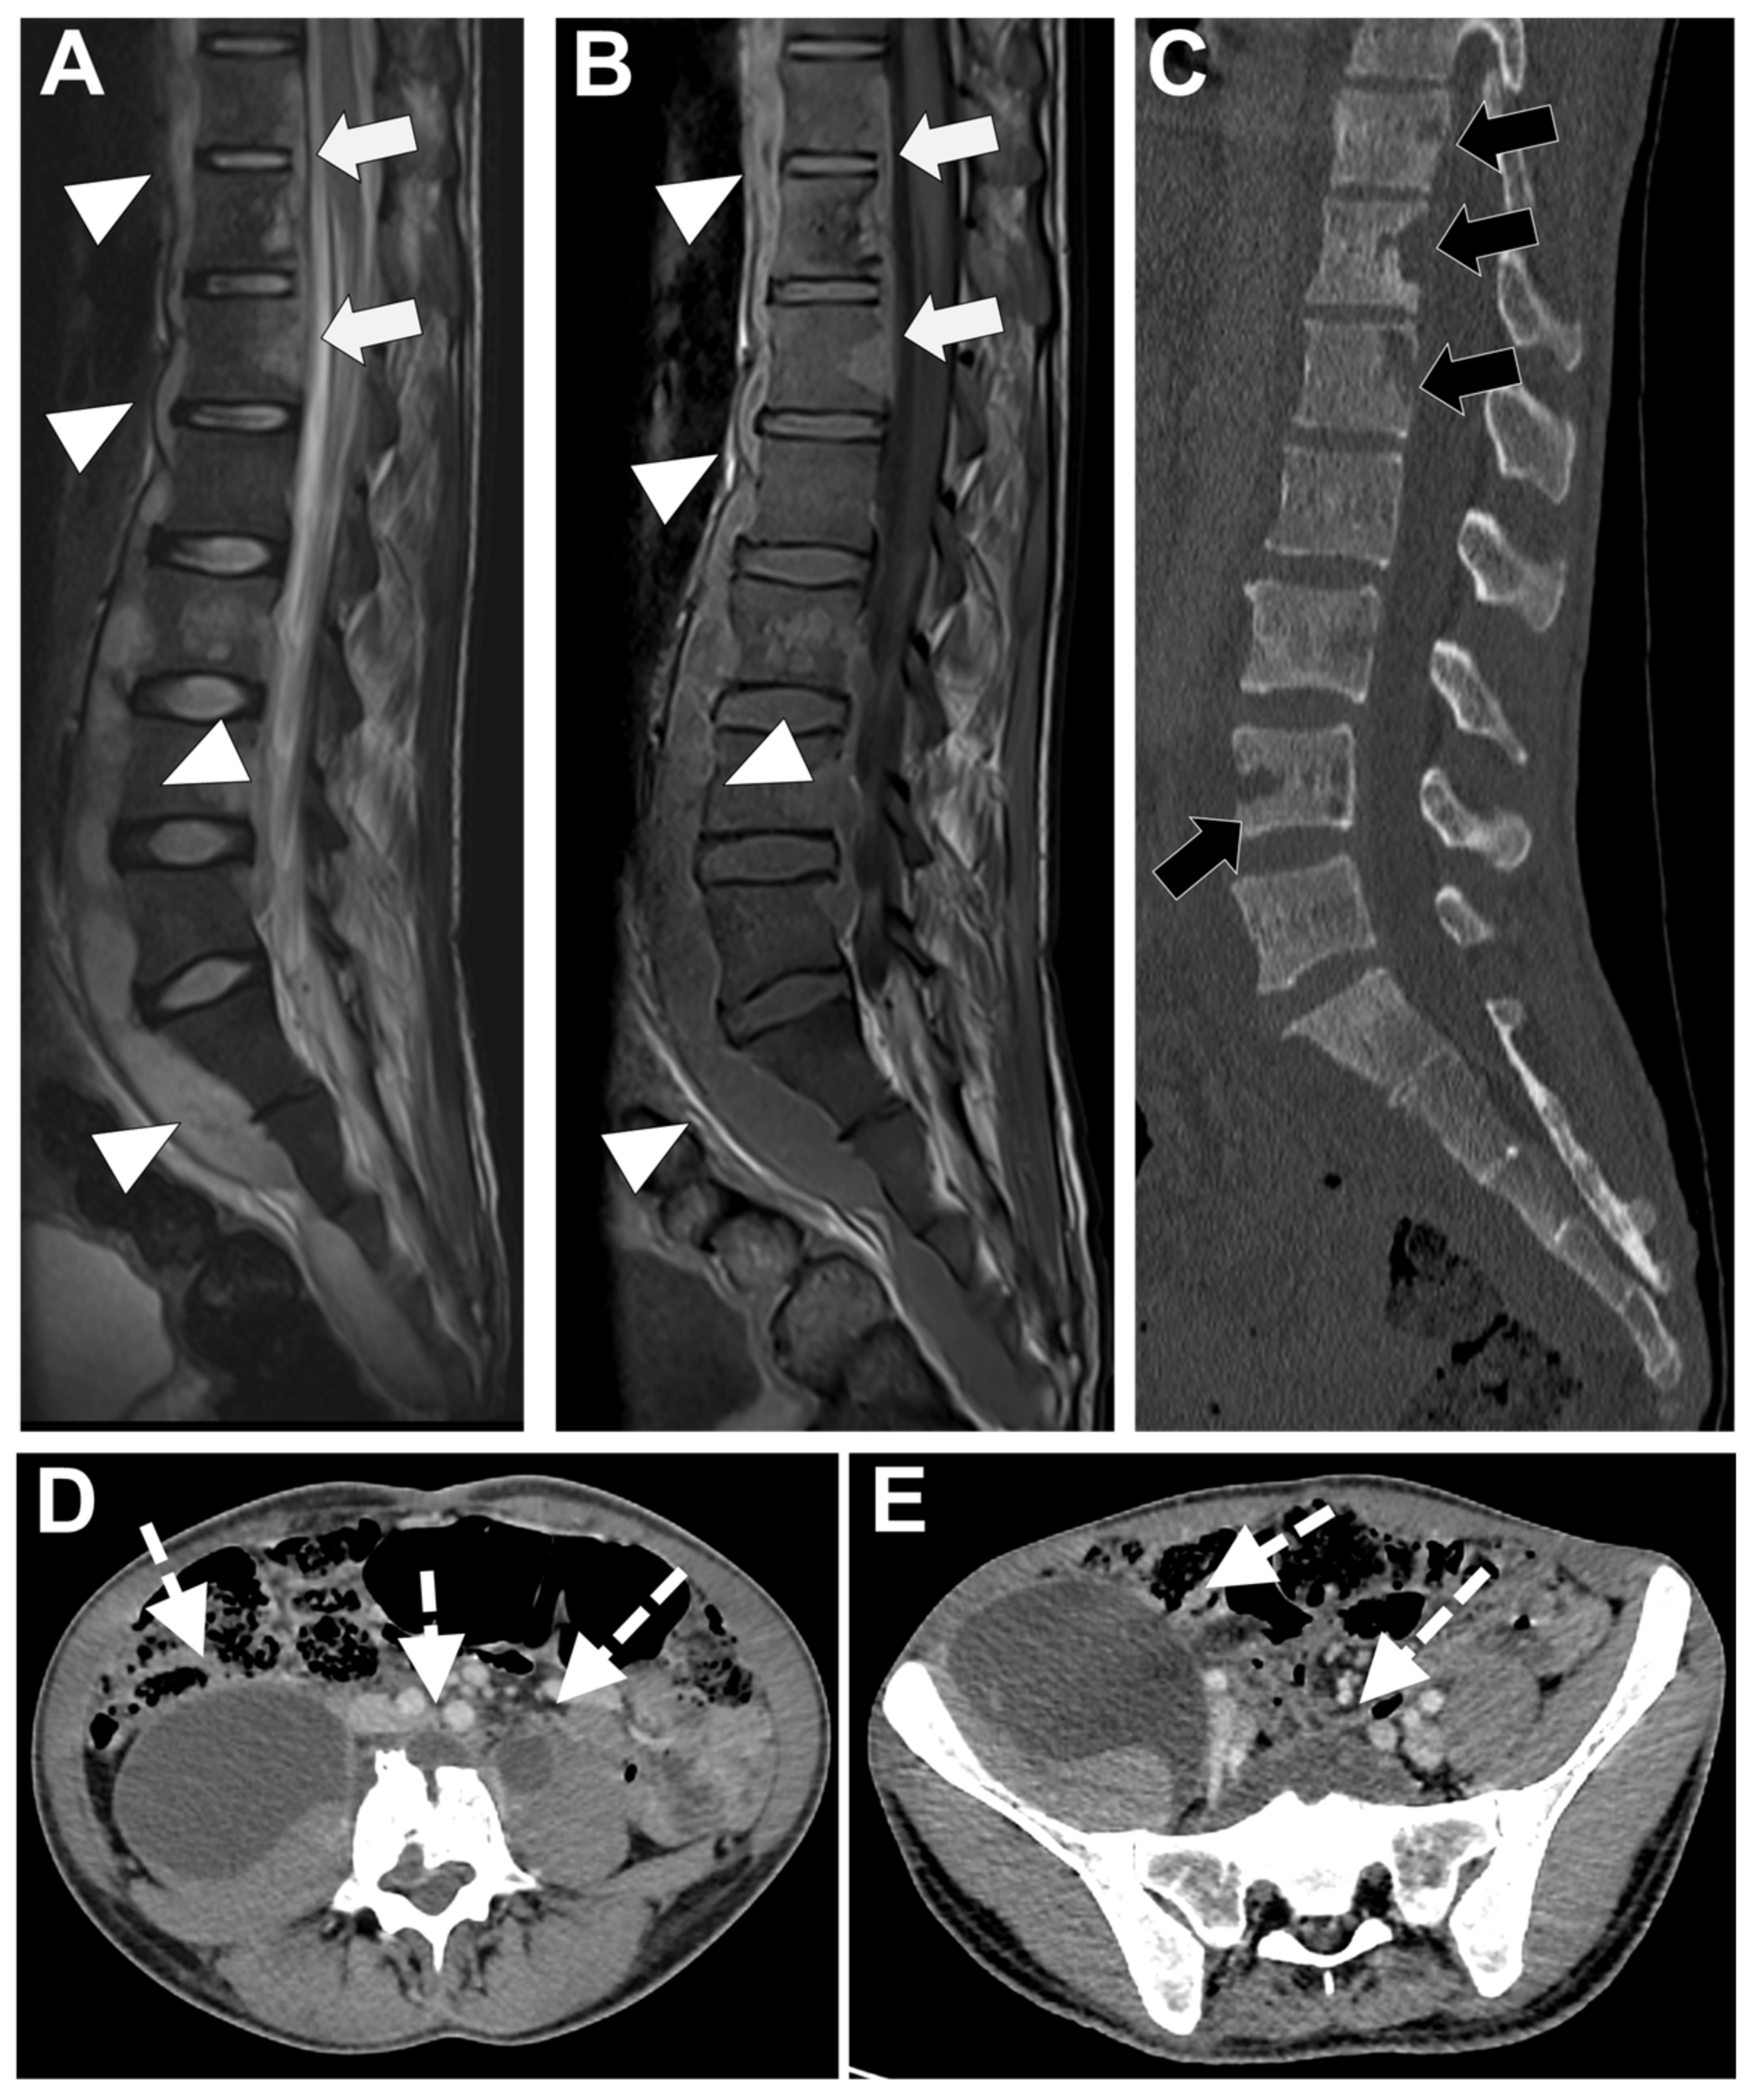

Figure 6. Tubercular spondylodiscitis. A 24-year-old man of Sudanese origin presented with thoracic and lumbar pain evolving for several months. An MRI was performed with (A) T2-weighted imaging (WI) and (B) contrast-enhanced (CE) T1-WI, as well as a CT-scan in bone kernel (C) and abdominal kernel after contrast medium injection (D,E). It demonstrates preserved disk but extensive sub ligamentous collections spreading along the anterior side of the thoracic and lumbar vertebral bodies (white arrowhead), but also along the posterior vertebral collateral ligament (white arrows) with large anterior and posterior erosions (black arrows). Please note the extensive collections spreading in the presacral space and along bilateral iliopsoas muscles without surrounding inflammation (white dashed arrows).